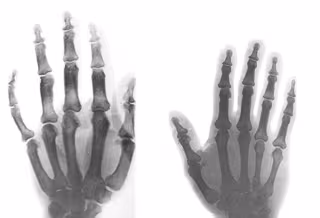

El estudio se ha centrado en mejorar el diagnóstico del acrogigantismo.

El estudio se ha centrado en mejorar el diagnóstico del acrogigantismo. - CSIC